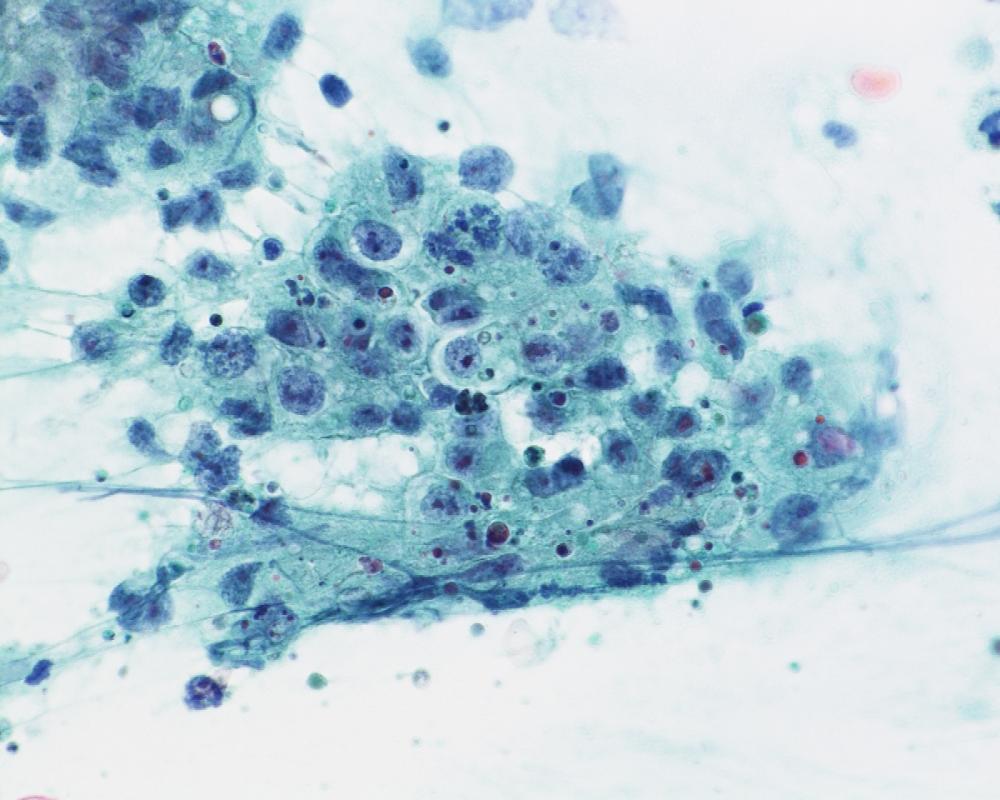

第40回日本臨床細胞学会九州連合会学会(大分)スライドカンファレンス症例4

種別:甲状腺

出題:松岡 優毅1、中島 正洋1,2 1長崎大学病院 病理診断科・病理部、2長崎大学原爆後障害医療研究所 腫瘍・診断病理学研究分野

| 年齢 | 80代 | 性別 | 女性 |

| 採取部位 | 甲状腺 | 採取方法 | 穿刺吸引細胞診 |

| 検体処理法 | ふきつけ |

既往歴・家族歴: なし

現病歴: 3か月前に7cm大の嚢胞性病変が指摘され穿刺吸引細胞診(Class III).増大、嗄声が確認され、再度穿刺吸引細胞診が施行された。なお、CT上では甲状腺から外方向性発育を示していた。採血データはThyroglobulinが84.3ng/mL(正常35.0以下)で、TSH、free T4、抗Tg抗体、抗TPO抗体は正常範囲内であった。

| 正解 | 4.Teratocarcinosarcoma |

▼選択肢及び投票結果

| 1.Adenomatous goiter | 10件 | (9.5%) | |

| 2.Papillary carcinoma | 27件 | (25.7%) | |

| 3.Intrathyroid thymic carcinoma | 48件 | (45.7%) | |

| 4.Teratocarcinosarcoma | 15件 | (14.3%) | |

| 5.Follicular neoplasm | 5件 | (4.8%) | |

| 投票総数 | 105件 | (100%) |